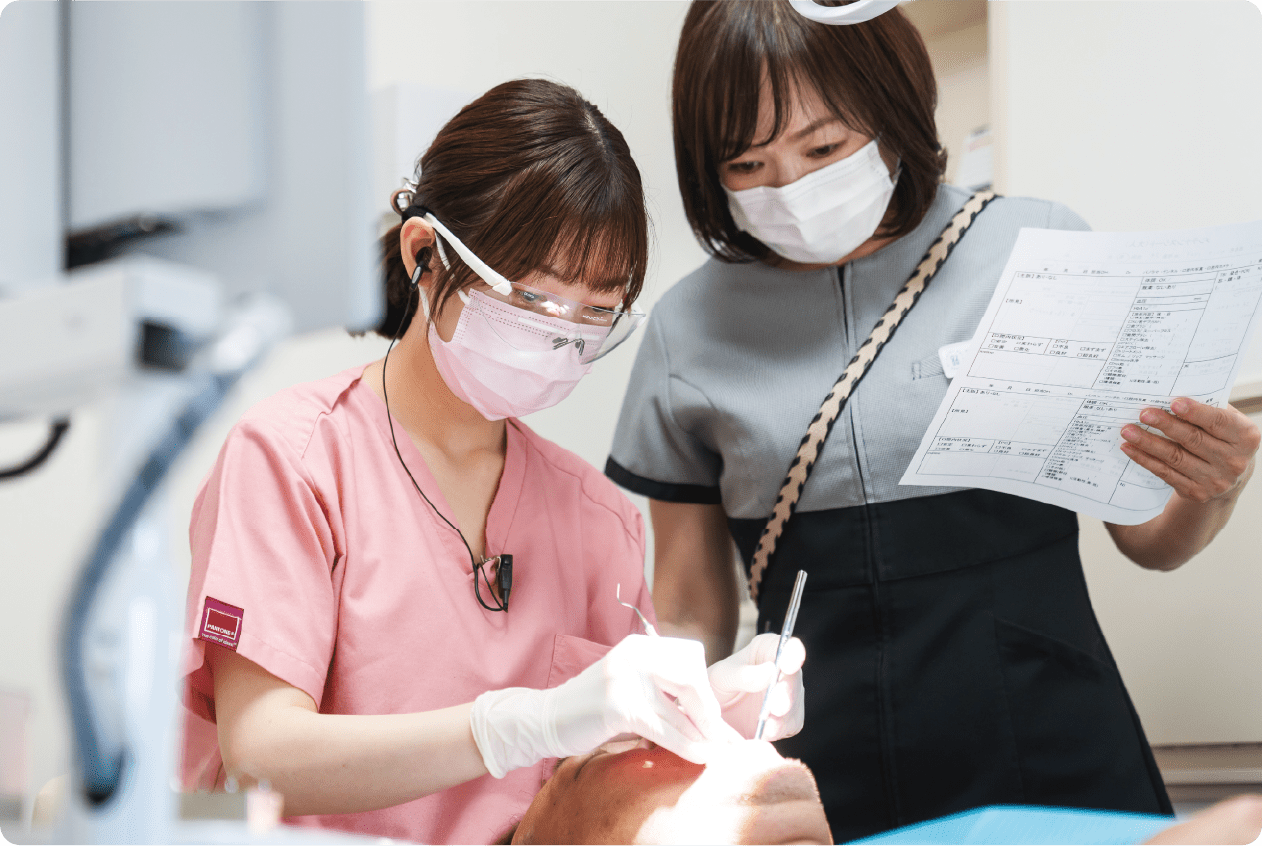

女性ドクターも在籍しています!

痛くない・なるべく抜かない・削らない治療を基本として、新しい技術を常に学び、大切な歯をお守りします。歯医者さんに行きたいと思ってもらえるように日々奮闘!

初診時はしっかり時間をとります!